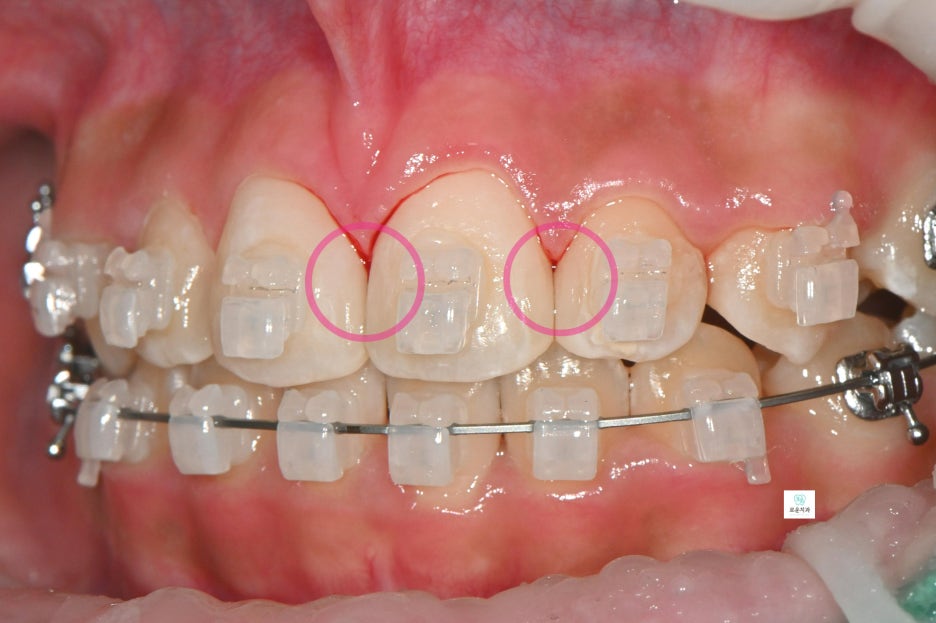

“교정 중 브라켓 주변 충치 치료 사례”

브라켓 주변에 여러 개의 충치가 발생하여

장치를 제거한 후 치료를 진행한 사례입니다.

한 치아 기준 약 3면 정도의 우식이 확인되어

충치 제거 후 수복 치료를 진행했습니다.

앞니 치료를 먼저 시행한 후

소구치와 대구치 부위 충치까지

순차적으로 치료를 완료했습니다.